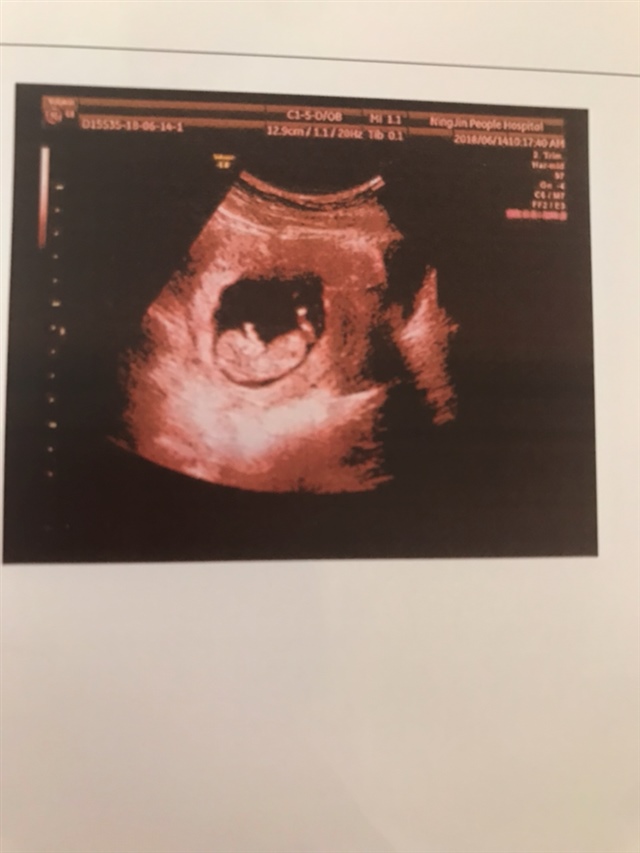

怀孕 孕7周+6天